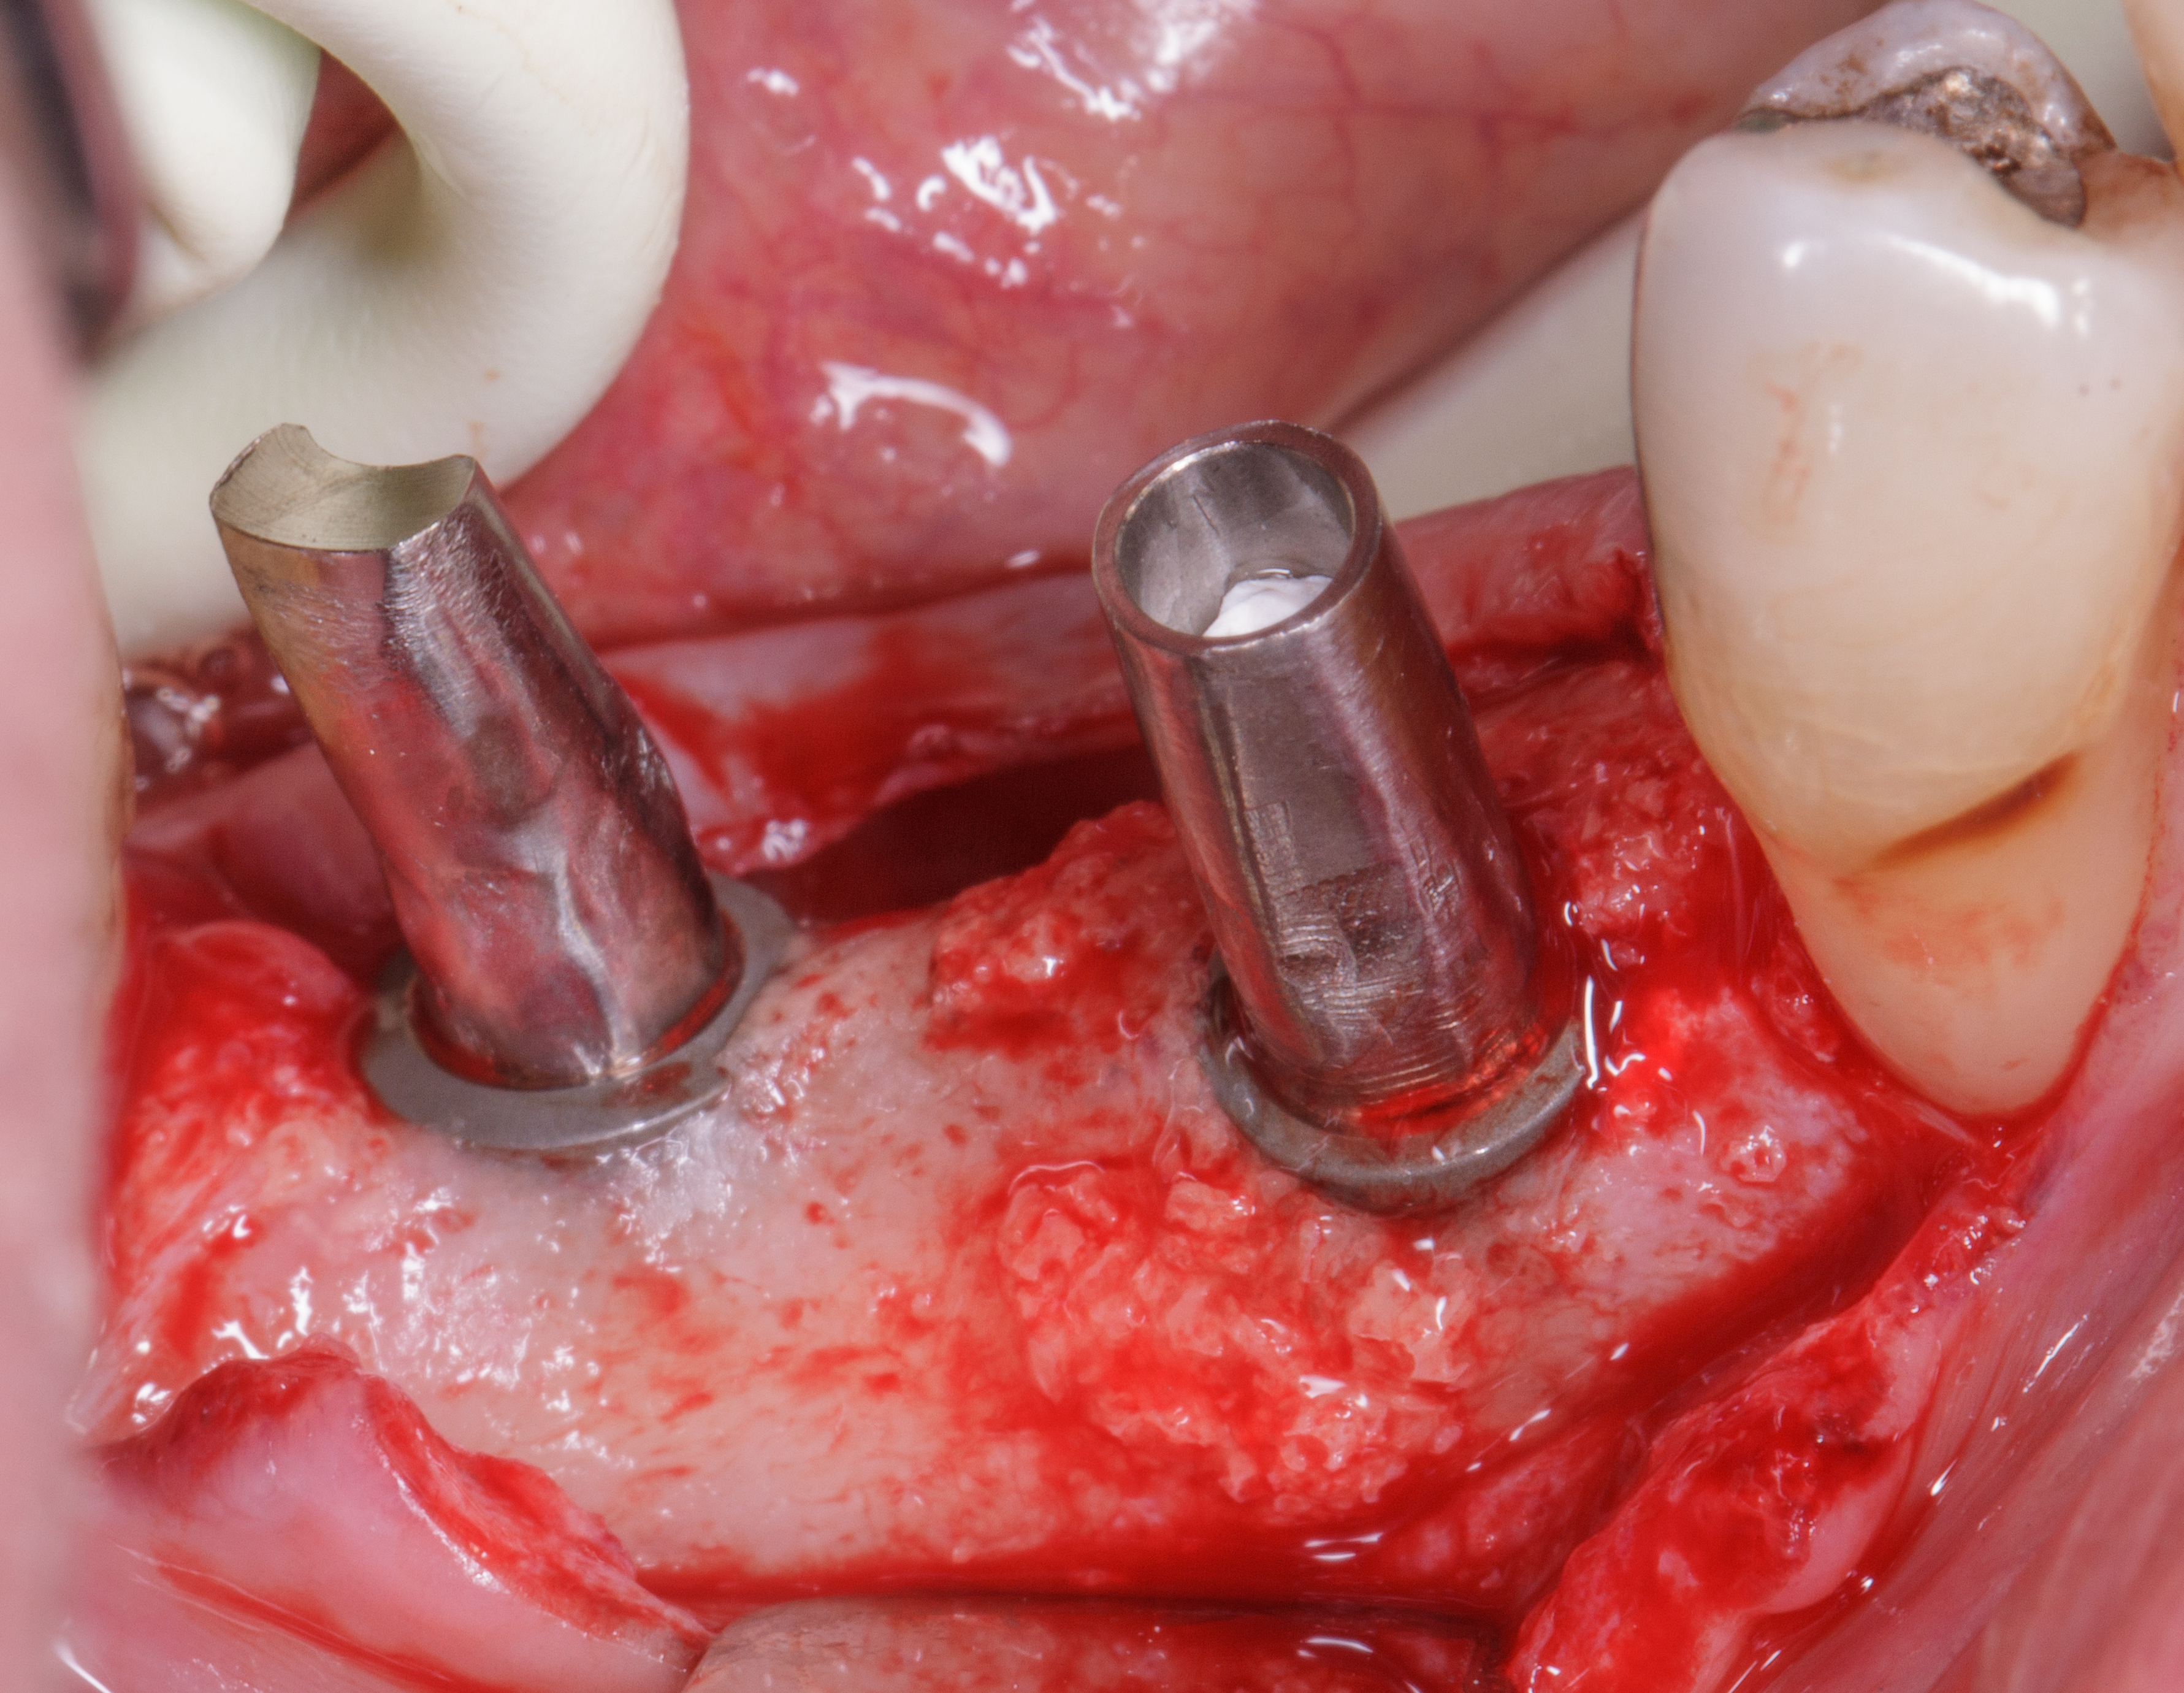

Dopo ulteriori quattro mesi si può procedere con l’ultima fase chirurgica di scopertura delle due fixture e di inserimento di abutment definitivi personalizzati.

Dopo l’apertura del lembo di accesso si evidenzia tessuto osseo corticalizzato anche nella zona vestibolare e crestale di 4.5. La visione occlusale consente di apprezzare la ricrescita ossea coronale alla vite tappo della fixture in 4.5 e del tessuto osseo vestibolare rispetto al bone housing. La misurazione ISQ di 4.5 restituisce l’alto valore di 86 (Figure 23-24).

Vengono inseriti due abutment protesici in titanio personalizzati con tecnica di preparazione verticale e una matrice eterologa di natura dermica (Osteobiol® Derma 2 mm) viene inserita a ponte sui due abutment per consentire di avere maggior tessuto cheratinizzato perimplantare. La sutura a punti staccati lascerà guarire una parte della matrice dermica per seconda intenzione (Figure 25-26).